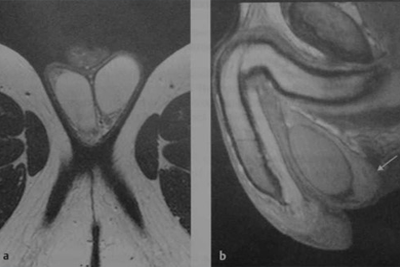

Магнитно-резонансная томография мошонки - одно из самых информативных диагностических исследований мужской мочеполовой системы. После сканирования на томографе пациент получает диск с объемными 3D-снимками, на которых можно увидеть многие заболевания органов мошонки: яичек, придатков яичек, семявыводящих протоков и сосудов, расположенных поблизости. Данное исследование совершенно безопасно, кроме того с его помощью можно «поймать» заболевания на самой ранней стадии.

В некоторых случаях может потребоваться проведение МРТ с контрастированием. Его назначают, как правило, если есть подозрение на онкологические заболевания. Контрастное вещество вводят в вену непосредственно перед началом исследования - оно абсолютно безопасно для организма и помогает более детально на снимках увидеть границы и размеры патологии, а также поставить точный диагноз.